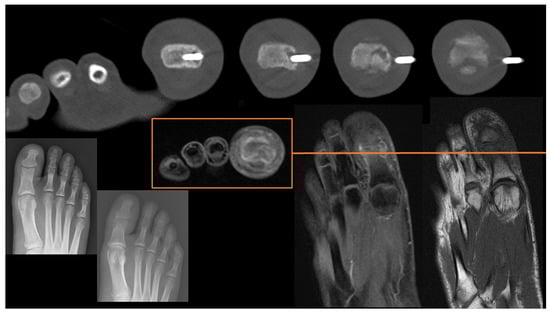

Hands and Feet